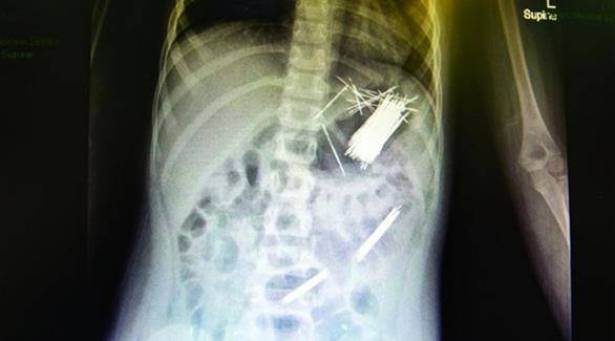

وكالات - الاقتصادي -تمكن فريق طبي في أحد المستشفيات بمدينة أبها السعودية من استخراج 50 دبوساً للشعر من معدة طفل عمره سبع سنوات، عن طريق جراحة المنظار، وفقاً لصحيفة الرياض اليوم الأربعاء.

قال مدير مستشفى أبها للولادة والأطفال الدكتور علي بن مستور القحطاني إن العملية استغرقت ثلاث ساعات، ونقل المريض لجناح التنويم بعد إجراء العملية بدون أي مضاعفات.